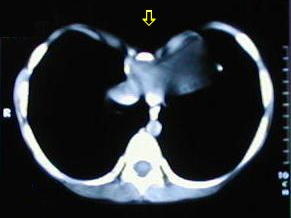

Tomografía de tórax

• Corte tomografico a nivel del tercio superior del torax, supracarinal.

• Corte tomografico a nivel carinal, comienza a insinuarse la depresión esternal.

• A medida que descienden los cortes, se observa la mayor depresión esternal.

• A nivel del tercio inferior se observa el punto de máxima depresion esternal.

• Corte a nivel del apéndice sifoides, observe la acentuada depresión por efectos de los cartilagos costales comunes.

• A nivel de la base del tórax los extremos de los arcos costales se observan protruyentes, debido al cambio de dirección de los cartílagos, ellos generalmente ceden, al resecar los cartílagos costales comunes.